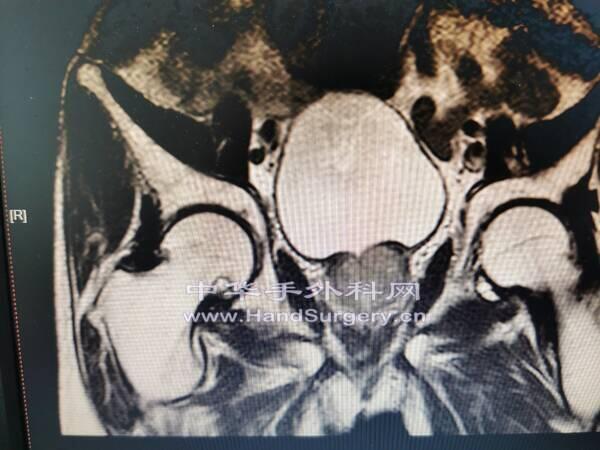

肛肠肿瘤患者,行盆腔核磁检查无意间发现股骨头肿物

囊肿影像局限,孤立,不在负重区,暂不考虑骨坏死。

会诊意见:考虑孤立性骨囊肿,不除外转移